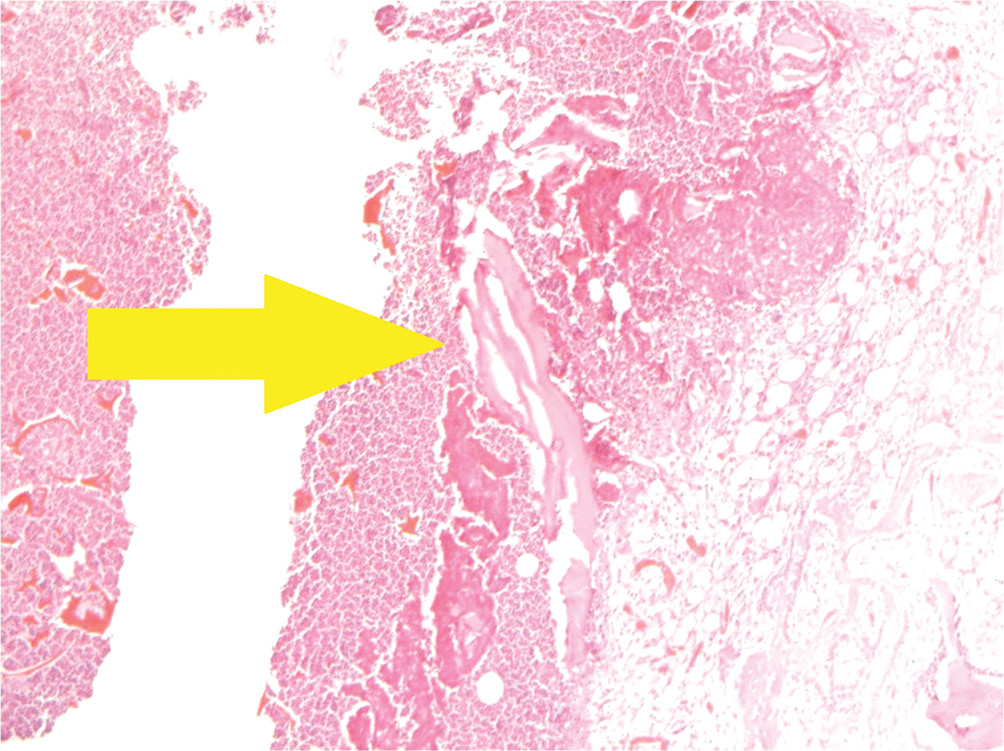

- Группа с губчатым материалом на основе хитозана и гидроксиапатита (рис. 5).

Рис. 5. Группа с протезом из хитозана с гидроксиапатитом: хрящевые островки среди грубоволокнистой ткани в зоне костного дефекта. Окраска гематоксилином и эозином, увеличение ×40

На 28-е сутки в зоне дефекта наблюдается участок, заполненный грубоволокнистой соединительной тканью с многочисленными гигантскими клетками инородных тел, сформированными вокруг небольших очагов из остатков исследуемого образца. К грубоволокнистой соединительной ткани прилежит костная мозоль с небольшими и немногочисленными более крупными хрящевыми «островками».

В группе ХГА отмечалась достаточно высокая степень резорбции со слабовыраженными проявлениями хронического воспаления в ответ на введение инородного тела. Наряду с этим в области дефекта были обнаружены островки хрящевой ткани, свидетельствующие в пользу стимуляции остеоиндукции, а также признаки формирования костной мозоли.